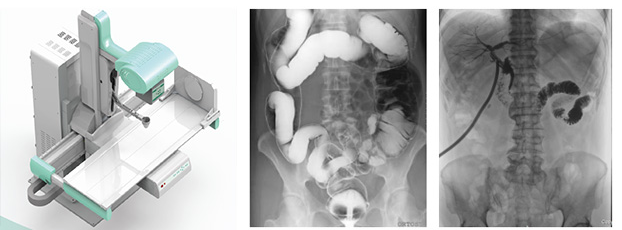

多功能动态dr由动态平板探测器、高压发生器、球管、运动机架、计算机与图像处理与传输系统组成,与传统数字化X线摄影技术相比,动态多功能dr摄影能在一个时间单位内低剂量高速获得多帧X线影像,通过图像算法处理系统后,极速输出一段连续动态影像(运动),实现所见即所得。

多功能动态dr可以理解为一种不同角度观察器官运动的X光视频。常规的静态dr更多的显示的是器官的投影像,单一角度单一时间点很难发现细微病灶。而多功能动态dr可以从不同的角度、时间来观察器官的运动,诊断准确率会大大提升。

多功能动态dr是集合拍片,透视,造影三种功能为一体的设备??梢远蕴厥獠≡畈课唤懈咚偈凳钡闫?,捕获高清病灶图,降低了漏诊误诊率。特别是对不能配合的患者,也能进行快速高效的检查,大大减轻了患者的痛苦。